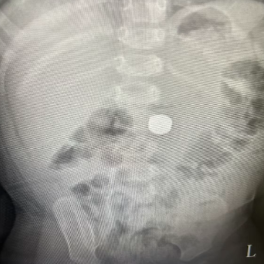

红网时刻新闻11月4日讯(通讯员 李姗 记者 戴丹)11月3日,中南大学湘雅三医院儿科再次收治1例11月大吞服电池的患儿,这是该科室自10月17日以来收治的第4例吞服电池的患儿。

“4个孩子中,年龄最大的4岁,最小的才10个月。”据医院儿科医生介绍,吞服的电池主要来源于孩子们玩具内的配置电池。

医生提醒:吞服电池严重者可导致消化道穿孔,危及生命,一旦发现,必须立刻就诊!